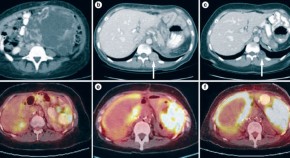

This Case Study describes the management of a patient with a fumarate hydratase (FH)-deficient type-2 papillary renal cell carcinoma. On the basis of results fromin vitro experiments, the authors decided to treat the patient with the glycolytic inhibitor 2DG (2-deoxy-D-glucose), a new anticancer drug that is currently in clinical development.